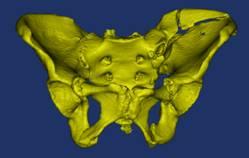

骨盆术前三维模型和模拟复位--正位前面观